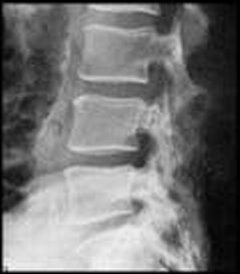

X-Rays

An X-Ray provides an image that can be used to evaluate bones, joints and degenerative lesions in the spine and extremities.